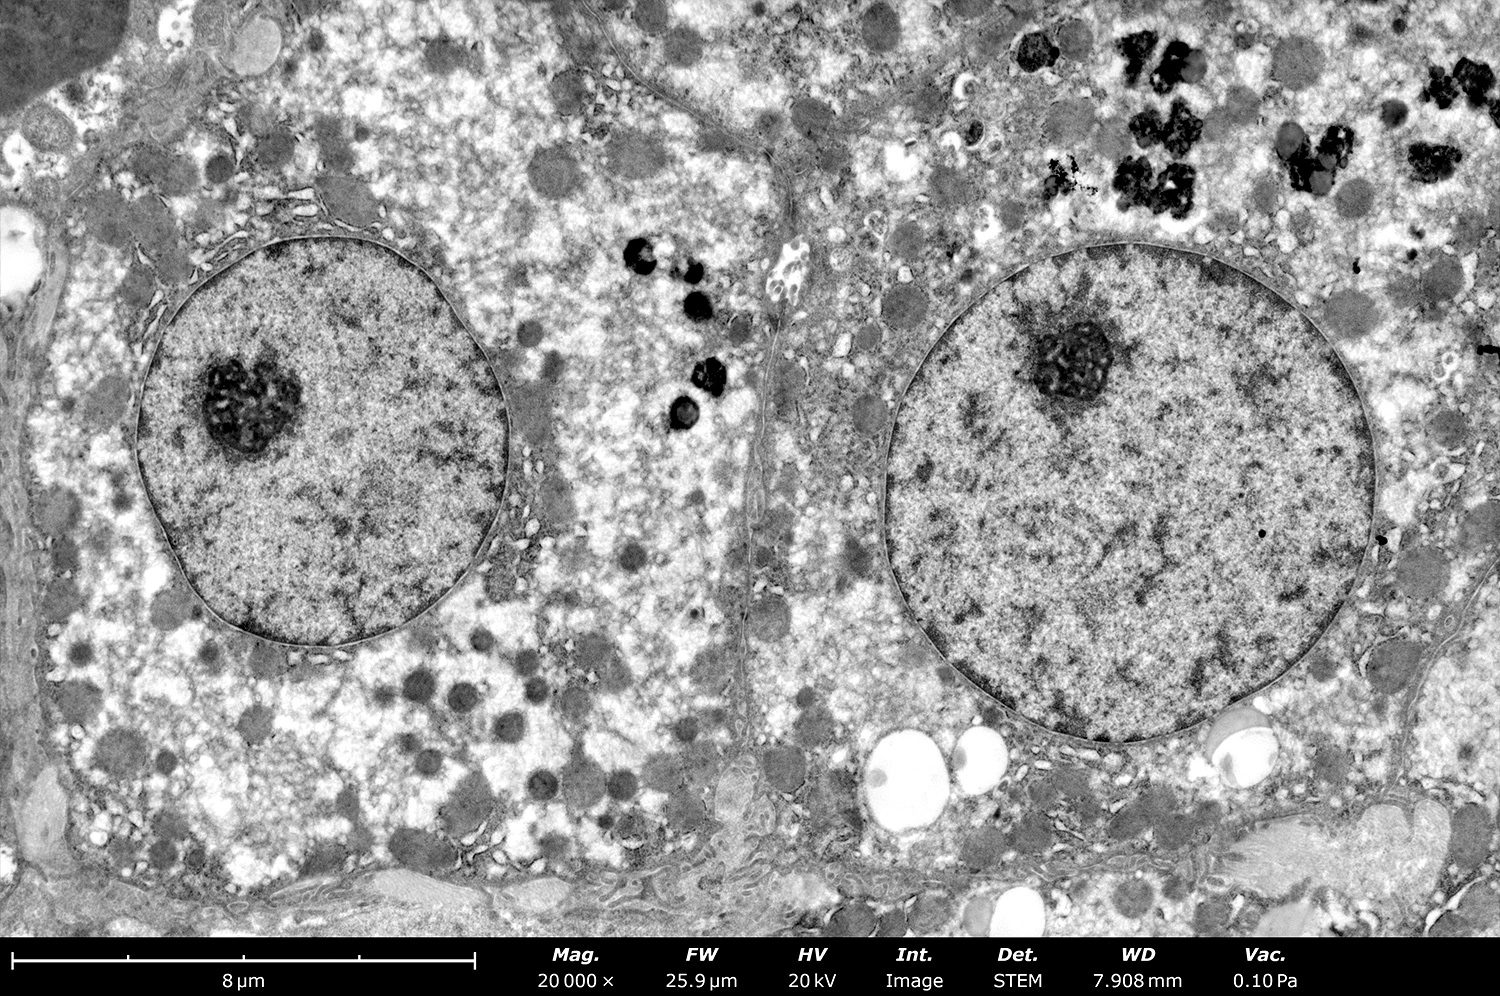

02 Electron Microscopy Era

The invention of electron microscopy in the 1930s dramatically increased resolution beyond the diffraction limit of light. Transmission electron microscopy (TEM) and scanning electron microscopy (SEM) allowed visualization of organelles and viral particles.

2 Electron Imaging

uses high-energy electron beams, rather than light, to magnify, visualize, and analyze the nanometer-scale structure of materials and biological specimens

Electron beams provide high-resolution ultrastructural information due to shorter wavelengths compared to visible light.